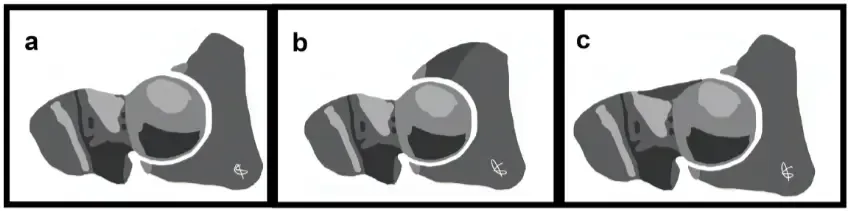

Schematic representation of hip: (a) normal hip, (b) hip with pincer-type impingement (the dark gray zone represents the acetabular over-coverage), and (c) hip with cam-type impingement (the dark gray zone represents the femoral head-neck junction abutment).